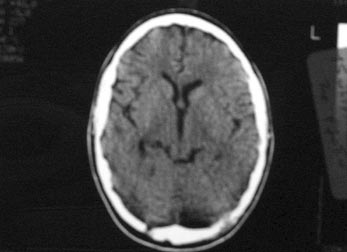

η CT εγκεφάλου εδόθη χωρίς παθολογικά ευρήματα, εκτός από σημεία φλεγμονής των

ηθμοειδών και μετωπιαίων κόλπων (εικόνα 1). Η ΟΝΠ που έγινε μετά το αρνητικό

Εικόνα 1. CT (1o 24ωρο):

Μετωπιαία κολπίτιδα με υδραερικό επίπεδο στον αριστερό μετωπιαίο κόλπο.

Εικόνα 2. CT (1o 24ωρο):

Πιθανή συλλογή υγρού στην μεσοημισφαιρική σχισμή.